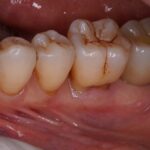

治療後

4ヵ月で最終的なセラミック冠を装着しています。